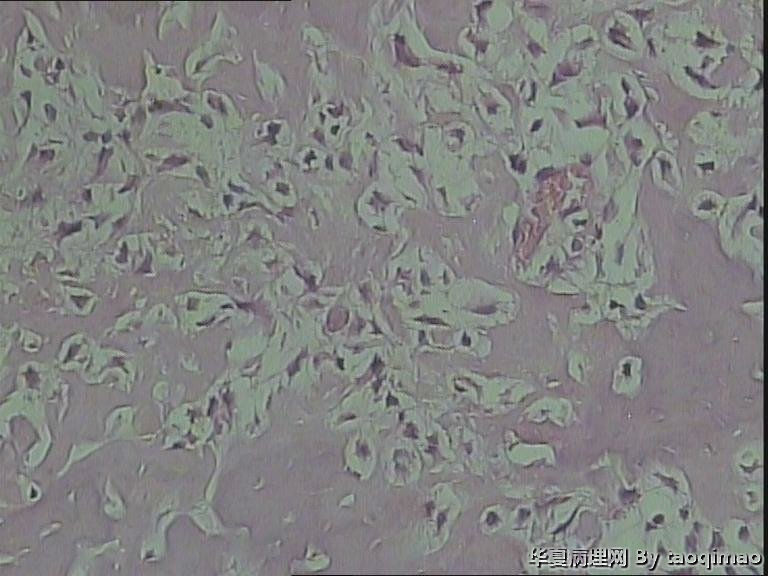

• 肋骨肿物,求助图3

图3

这是一部分容易取下来的肿瘤,其余部分还在脱钙中

患者女,31岁,胸部CT第八肋骨肿瘤,肿物在肋骨内突出骨外膜,大小2.3X1.5.切面灰白质韧

骨母细胞瘤。矿化不均要除外骨母细胞型骨肉瘤,虽然肿块小了点。还是找找核分裂,看看X线的好。